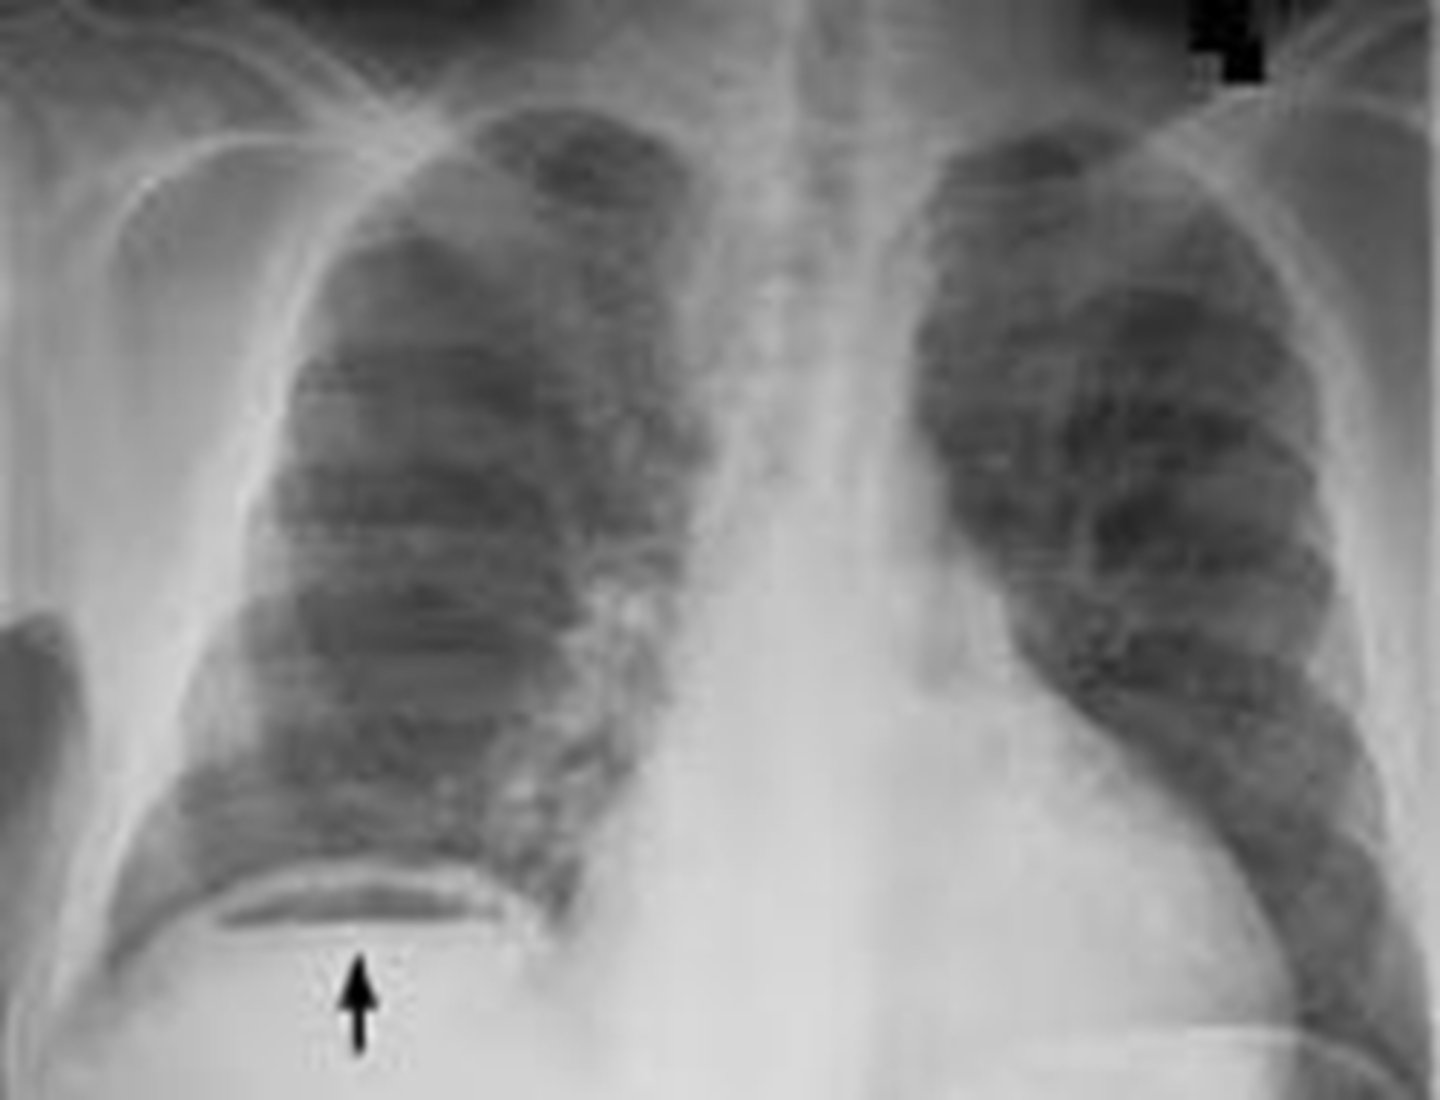

is perforation of a hollow viscus structure a medical emergency

yes

extraluminal air will rise to the highest part of the abdomen which is under the

diaphragm

crescentic lucency (extraluminal air)

types of extraluminal air

pneumoperitoneum, retroperitoneal free air, air in bowel wall, air in biliary system